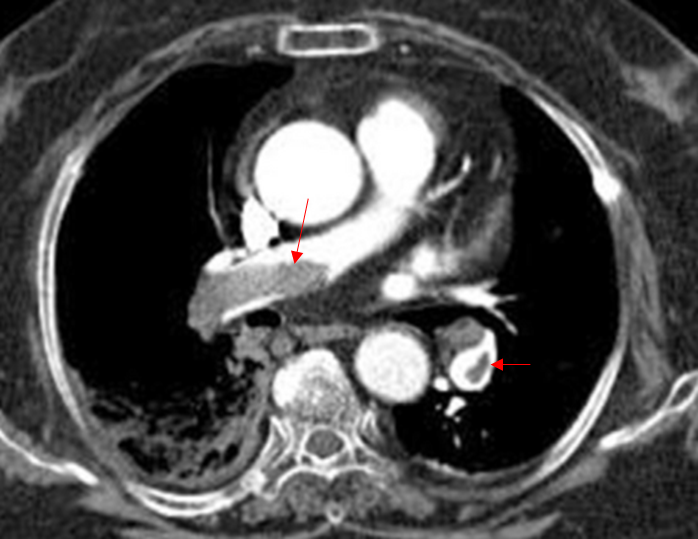

70세 남자가 1일 전부터 갑자기 숨이 찬다며 병원에 왔다. 2주 전부터 오른쪽 다리가 부었다고 한다. 식은땀을 흘리면서 숨을 몰아쉬고 있다. 40갑 ∙ 년의 흡연자이고 복용하는 약은 없다. 혈압 70/50 mmHg, 맥박 118회/분, 호흡 26회/분, 체온 36.9℃이다. 가슴 청진에서 호흡음은 정상으로 들린다. 가슴 컴퓨터단층촬영 사진이다. 치료는?

Img | CT: Thrombus in pulmonary a., r/o partial Rt. lung infarction |

CT상 PTE가 확인되며, V/S이 불안정하며, thrombolysis의 금기증이 없으므로 IV t-PA를 투여한다.

• DVT 증상, 빈맥으로 보아 PTE가 매우 의심될 뿐만 아니라, V/S이 불안정하므로 바로 CT를 촬영했다. CT상 pulmonary a. 내부에 큰 혈전이 보이며, PTE로 확진할 수 있다.

• PTE의 치료는 혈역학적 안정성에 따라 나뉘는데, 현재 저혈압이 있으므로 신속한 reperfusion이 필요하며, thrombolysis의 금기증이 없으므로 혈전용해제인 t-PA(tissue plasminogen activator)를 투여한다.